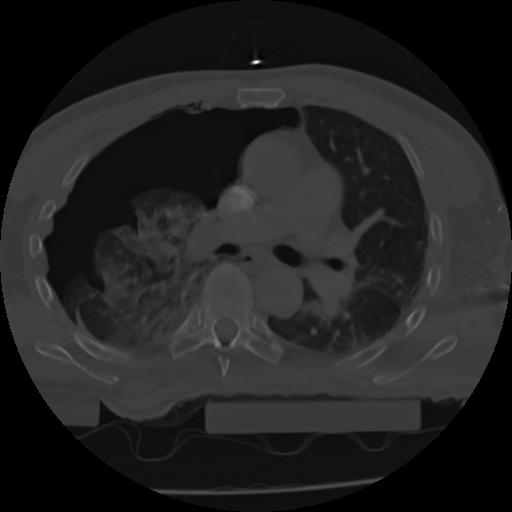

21 ANGIO,CE,Axial,3.0,ANGIO,,